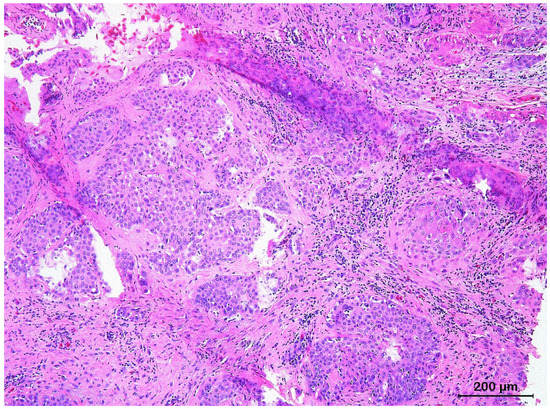

3.2. Squamous Cell Carcinoma and Its Histological Variants

3.3. Basal Cell Carcinoma and Its Histological Variants